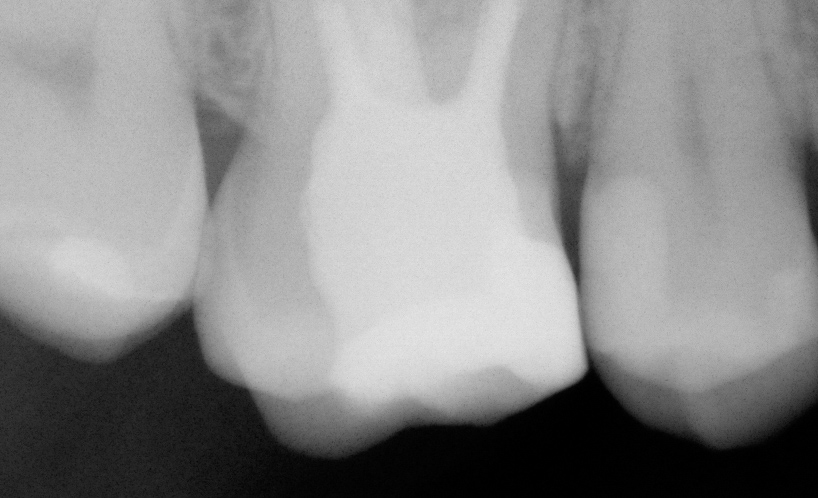

Two weeks later, the canals were irrigated with 5.25% sodium hypochlorite with ultrasonic activation (10 cycles), and permanent obturation of the root canals was performed using AH Plus sealer and gutta-percha.

The coronal restoration was completed using a fiberglass-based material (EverX) and NeoSpectra A3 composite.